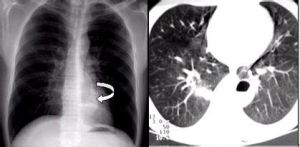

可根據病史及臨床表現。X線檢查對診斷有很大幫助。囊腫在X線片上顯示為一清晰圓形或卵形的透明陰影,邊緣整齊,周圍常呈現一明顯白色骨質反映線,但角化囊腫中有時邊緣不可不整齊。